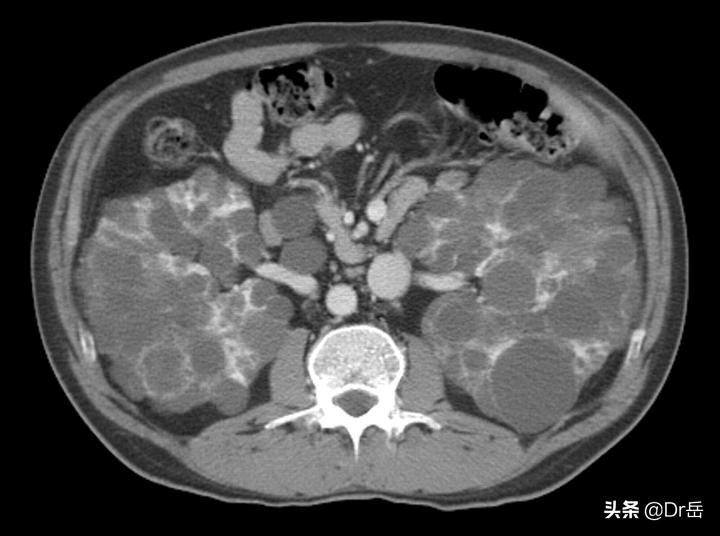

多囊肾最直接的诊断就是影像学,做个肾彩超、CT一目了然。有一半的患者合并有多囊肝,影像学也是能够发现的。前面提过多囊肾虽然是遗产病,但是发病是在中青年,也是就是说如果父母有多囊肾的,一定让孩子定期检查彩超,做到早发现,为治疗做准备。